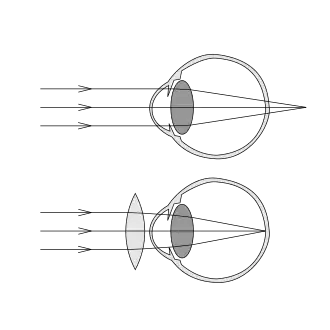

Этот дефект заключается в том, что из-за аномалии рефракции в покое аккомодации изображение фокусируется не на сетчатке глаза, а за сетчаткой. В молодом возрасте, при не слишком высокой дальнозоркости, обычно удаётся сфокусировать изображение на сетчатке с помощью напряжения аккомодации. Дальнозоркие люди часто испытывают головные боли при выполнении работы вблизи.